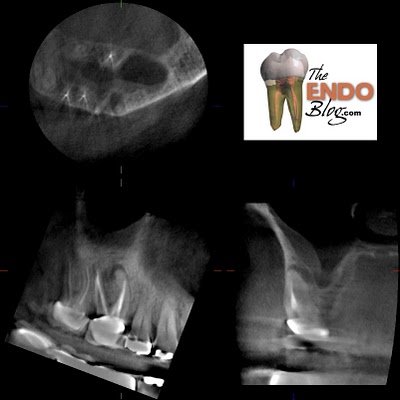

Here’s an example of a routine CBCT scan that I did prior to endodontic surgery. This scan gave me added information, that then changed the treatment plan and give us better prognosis.

This patient presented for evaluation. The teeth are asymptomatic, but a lesion seen by his general dentist. The lesion is obviously on the MB root of #3, with ledged MB canal. The crown margins looked good and since the MB canal is ledged, we were planning to treat this tooth with an apicoectomy. I recommended a routine, pre-surgical CBCT to evaluate the root anatomy, sinus proximity and buccal bone contours.

This slice through the MB root shows that there is a missed MB#2 canal.